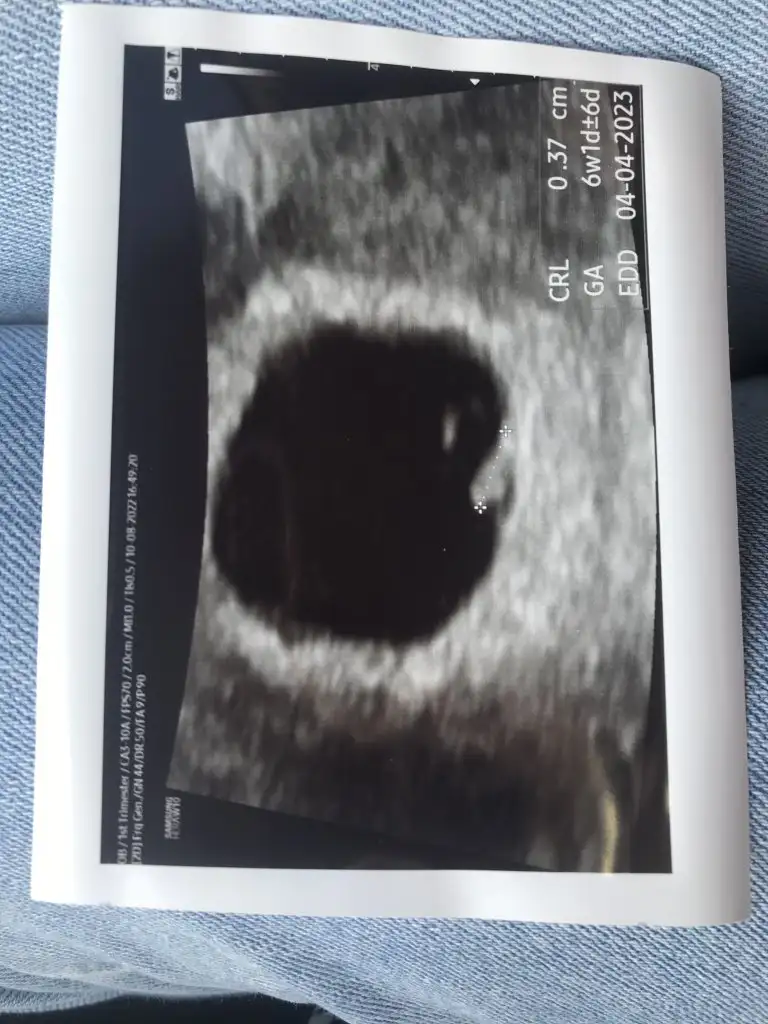

Bunda yolk sac gayet görünüyo kuzum, içinde yuvarlak bi şey var bakCanim bende de öyle hatta sende içinde bise var baya net bende pek yok oda, yolk sac fln doktora sormadim unuttum, doktorda hicbise demedi , yarin kalp atışım var o zamana netleşir zaten.

Yolk sac kesenin içinde küçük içi boş bi yuvarlak oluyo canım. Seninkinde göremedim ama boyutu küçük olduğundandır, biraz daha büyüyünce görünür. Ya da doktor görmüştür ama yolk sacın olduğu açıdan çekememiştir fotoğrafıBen de koyayım ama en minili benim ki sanırım :) yolk sacını nasıl anlıyorsunuz bizi de aydınlatabilir misiniz

O gözüken nokta gibi şey mi canim, simdi dikkatli bakınca sen deyince oval bise gördüm hakikaten aaaaBunda yolk sac gayet görünüyo kuzum, içinde yuvarlak bi şey var bak

Evet canım dikkatli bakarsan kesenin içinde içi boş bi yuvarlak var :)O gözüken nokta gibi şey mi canim, simdi dikkatli bakınca sen deyince oval bise gördüm hakikaten aaaa

1 haftadır bakıyordum görmedim valla sen deyince gördüm bu kadar olurEvet canım dikkatli bakarsan kesenin içinde içi boş bi yuvarlak var :)